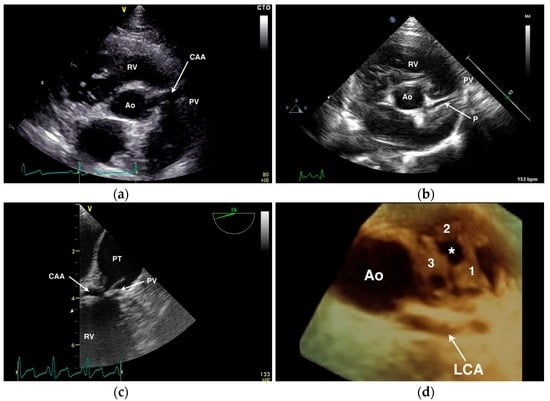

4.1. Anomalous Origin from the Aorta

4.2. Anomalous Origin from the Pulmonary Trunk

- Navalon, I.; Pradelli, D.; Bussadori, C.M. Transesophageal echocardiography to diagnose anomalous right coronary artery type r2a in dogs. J. Vet. Cardiol. 2015, 17, 262–270. [Google Scholar] [CrossRef] [PubMed]

- Visser, L.C.; Scansen, B.A.; Schober, K.E. Single left coronary ostium and an anomalous prepulmonic right coronary artery in 2 dogs with congenital pulmonary valve stenosis. J. Vet. Cardiol. 2013, 15, 161–169. [Google Scholar] [CrossRef] [PubMed]

- Laborda-Vidal, P.; Pedro, B.; Baker, M.; Gelzer, A.R.; Dukes-McEwan, J.; Maddox, T.W. Use of ECG-gated computed tomography, echocardiography and selective angiography in five dogs with pulmonic stenosis and one dog with pulmonic stenosis and aberrant coronary arteries. J. Vet. Cardiol. 2016, 18, 418–426. [Google Scholar] [CrossRef] [PubMed]